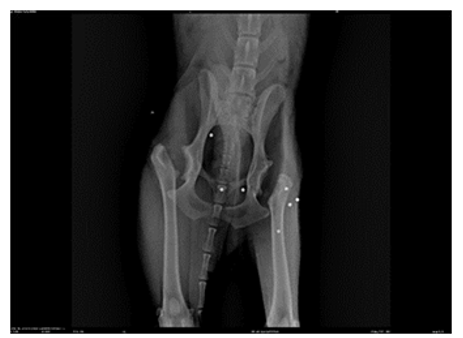

Figure 4: X-ray After the Second Surgery -(Ventro Dorsal Position) with Bilateral Excision of the Femoral Head and Neck

In Figures 2 and 3, we observe the bilateral coxofemoral joint in a ventrodorsally and lateraly view, where severe bilateral coxofemoral joint incongruence is noted, with evident femoral head luxation in the left limb. The presence of osteophytes along the acetabular margins and bilateral atrophy of the thigh muscles are also observed. In Figure 4, the absence of the coxofemoral joint is evident, showing the radiograph following the second surgery, where bilateral ostectomy was performed. The presence of acetabular osteophytes and bilateral atrophy of the thigh muscles is highlighted

The canine was discovered abandoned near the municipal kennel and subsequently rescued. Following a medical examination and X-rays, the dog was diagnosed with severe coxofemoral dysplasia, necessitating femoral head ostectomy due to joint dislocation (Figures 2 and 3). The initial surgery took place in March 2022 the left limb followed by a subsequent procedure in August 2022. (figure4)for the rigth limb.

Figure 5: X-ray after the Second Surgery. -(Ventro Dorsal Position) with Bilateral Excision of the Femoral Head and Neck Post 10 Session, Where you Can See Greater Muscle Mass in Relation to Photo 04